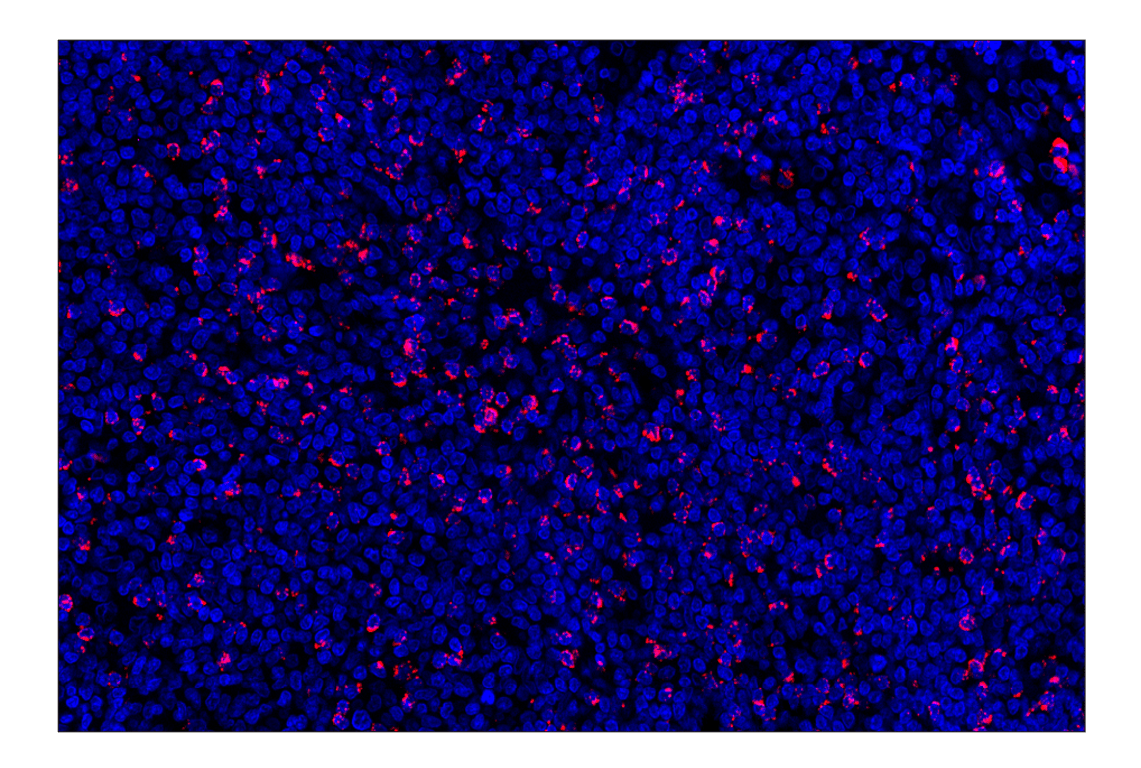

NKG7 (F4V5I) Rabbit Monoclonal Antibody (Alexa Fluor® 555 Conjugate) #13036

Immunohistochemistry (Paraffin) 1:50 - 1:200

NKG7 (F4V5I) Rabbit Monoclonal Antibody (Alexa Fluor® 555 Conjugate) recognizes endogenous levels of total NKG7 protein. Non-specific staining was observed in pancreatic islets by immunohistochemistry.